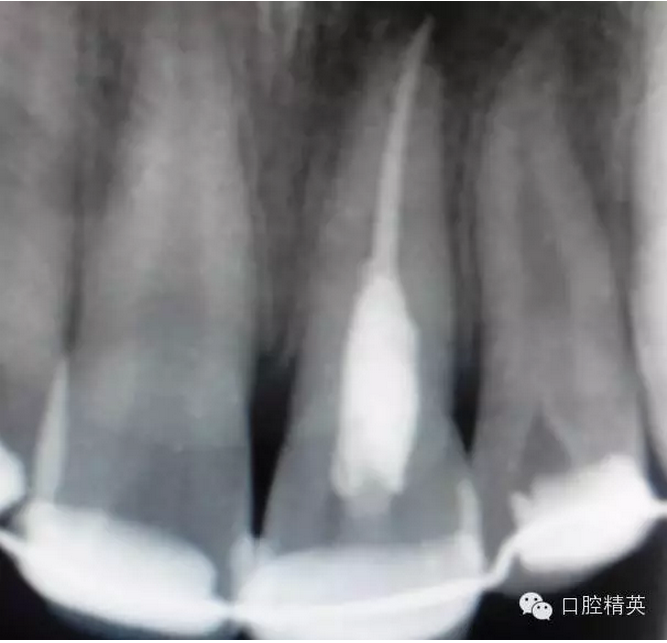

x線(xiàn)檢查:21牙槽窩空虛,窩內(nèi)未見(jiàn)其他遺留物。

圖3.患者21根尖片,牙槽窩空虛,無(wú)變形。